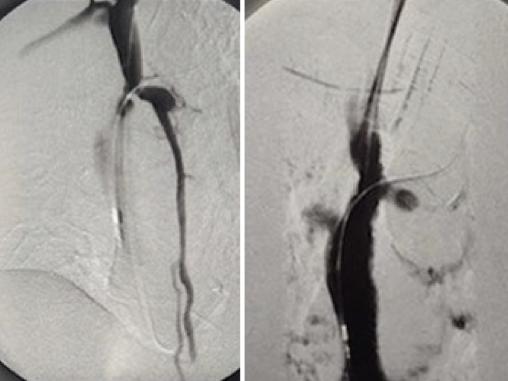

Une tomodensitométrie thoraco-abdomino-pelvienne avec et sans injection est réalisée. Elle retrouve une veine cave sténosée d’aspect très serré (fig. 2), expliquant les varices thoraco-abdominales. Ces dernières servent de réseau de suppléance au système cave supérieur et drainent ainsi la partie supérieure du corps. Le patient est hospitalisé en chirurgie thoracique et cardiovasculaire afin de bénéficier d’une dilatation cave supérieure par voie endoluminale (fig. 3), sans pose de stent.